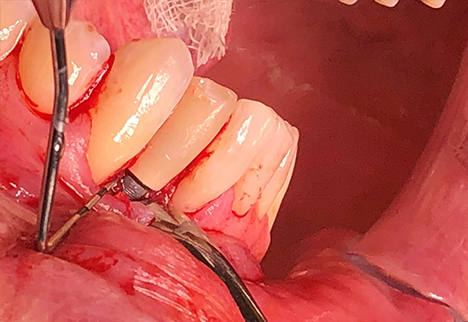

Surgical Procedure

Initial Surgery:

Under local anesthesia and intravenous conscious sedation, a full-thickness mucoperiosteal flap was raised to fully expose the implant and surrounding bone defect. The implant crown was removed, and the implant itself was atraumatically removed using a thin fissure with sterile saline irrigation and a reverse-torque technique to minimize trauma to the alveolar bone and prevent further bone loss. Granulation tissue was debrided using mechanical curettage and copious sterile saline irrigation was performed. The circumferential defect was measured at approximately 6 mm on the mesial and 8 mm on the mesial aspect of the implant with iatrogenic removal of the buccal cortical plate prior to implant removal.

Guided Bone Regeneration:

Guided bone regeneration (GBR) was performed using an allograft particulate bone substitute (a mineralized/demineralized blend). The graft material was carefully packed into the defect to reestablish the alveolar ridge contour. A resorbable collagen membrane was then placed over the graft to protect the site and enhance regeneration. The flap was advanced, with periosteal release, and secured with tension-free closure using PTFE sutures.